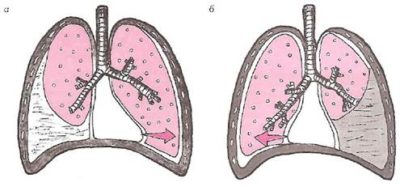

Осумкование может быть первичным и вторичным. Под первым понимают скопление экссудата между уже существующими спайками в плевре. При вторичном осумковании плевральный выпот отделяется, и образуются новые сращения.

В основе этого явления лежит оседание фибрина на листках плевры, с последующей организацией и созданием «сумок», уменьшающих объем плевральной полости и площадь, на которой происходит резорбция жидкости.

Экссудат может осумковываться частично или полностью. При первом варианте плевральные спайки образуют 1-2 стенки «сумки», вследствие чего возможно перемещение жидкости при смене положения тела. При полномосумковании экссудат ограничивается сращениями листьев плевры со всех сторон. На рентгене он будет выглядеть одинаково, независимо от положения пациента. Кроме того, различают одиночные и множественные зоны осумкования. Недуг бывает односторонним или двухсторонним.